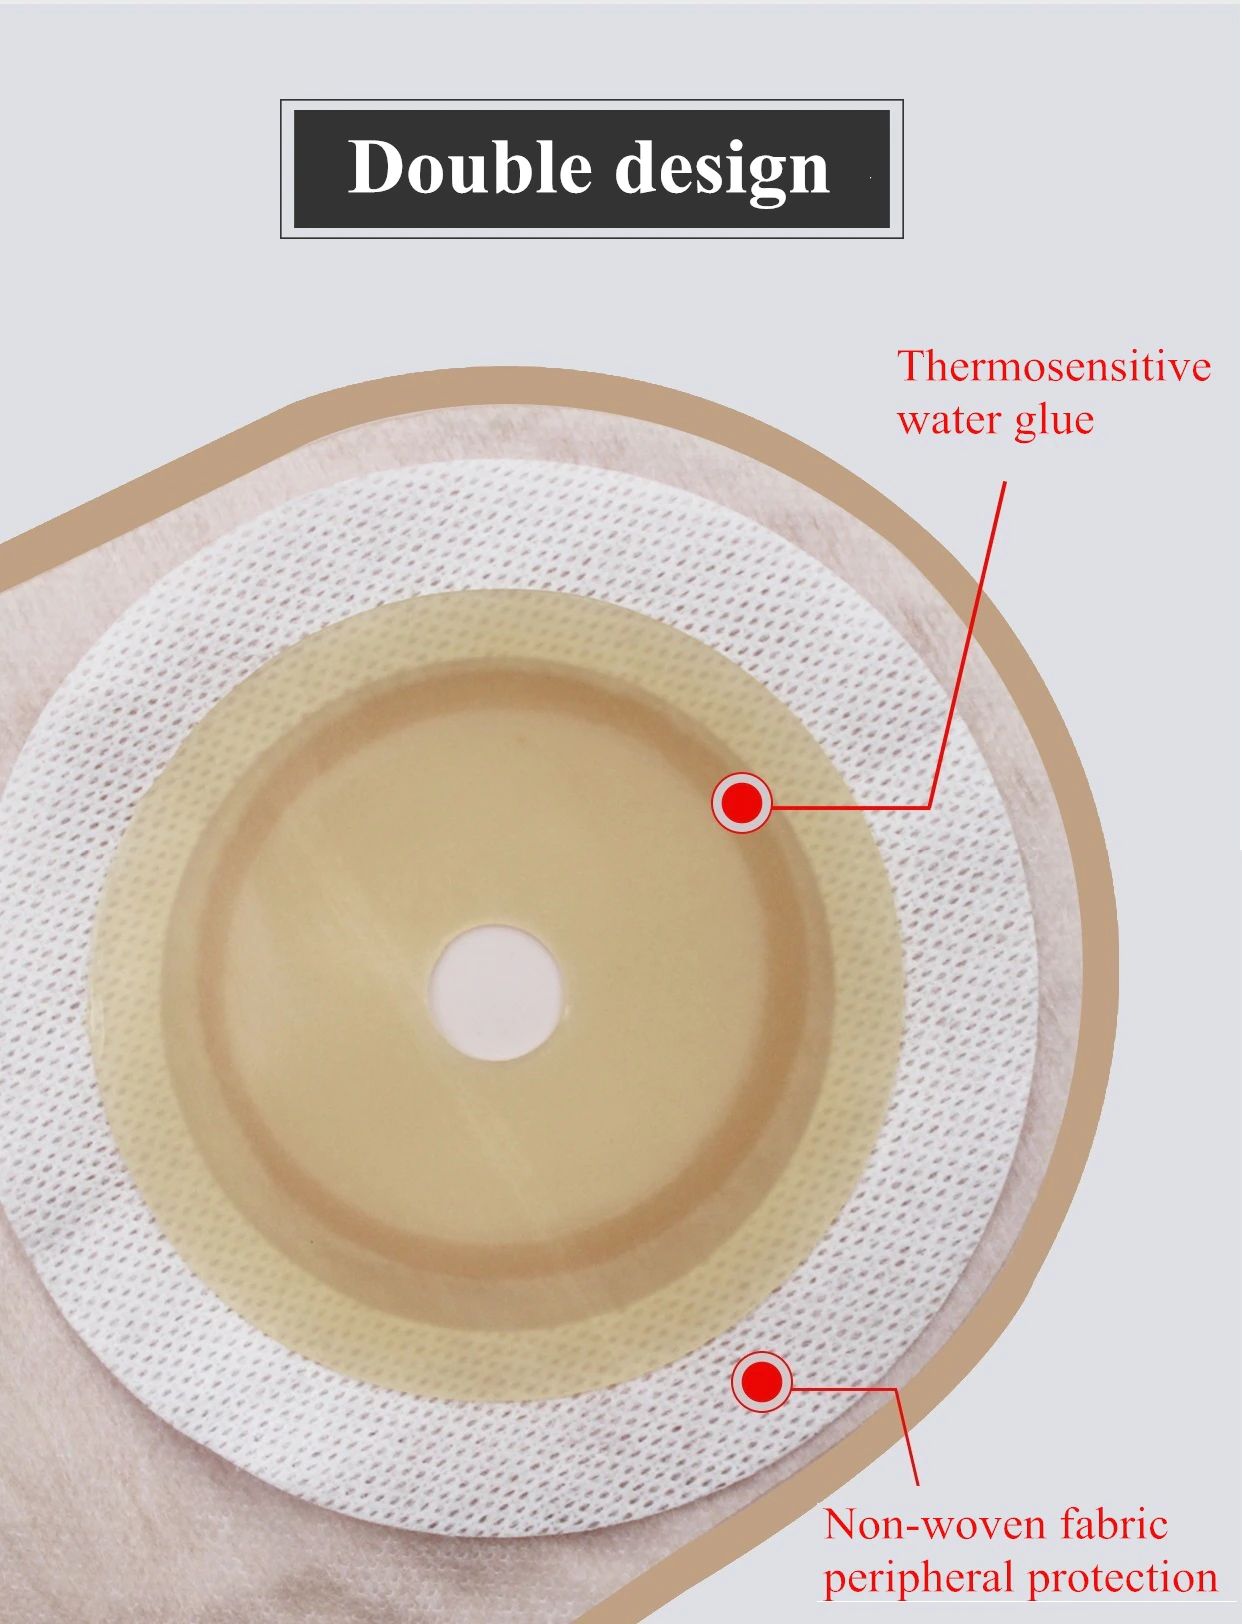

Descripción del producto La bolsa de cuidado de ostomía combina la barrera de la piel y la bolsa de colección en un sistema simple y fácil de administrar, proporcionando una gran simplicidad. La bolsa de colostomía es fácil de aplicar con el cierre de Velcro adjunto, proporcionando seguridad, ya que los sujetadores de plástico se bloquean en su lugar, fáciles de vaciar y irrigar. El propósito de reemplazar la ostomía 1. Observa la mucosa del estoma, las suturas circundantes y la piel circundante. 2. Limpia la piel alrededor del estoma, reduce el olor y aumenta la comodidad. 3. Evita que el agua fecal contamine la incisión abdominal a través de la fuga del chasis. 4. Si hay impregnación, asegúrese de reemplazarla a tiempo. Se recomienda cambiar el tiempo de 3-5 días para garantizar una respiración efectiva de la piel. Sentido común de la vida ostomía 1. Comer uniformemente, beber mucha agua y comer más verduras y frutas. 2. Evite comer demasiado rápido y tragar aire, masticar alimentos lentamente, Evite hablar mientras come, evite comer demasiado de una vez. 3. Evite las comidas con alto contenido de fibra y evite el bloqueo del estoma. 4. La ropa es suave y cómoda. 5. Evita el trabajo para aumentar la presión abdominal (como extraer objetos pesados). 6. Mantenga su estado de ánimo feliz. Paquete 10 unids/caja bolsa de ostomía